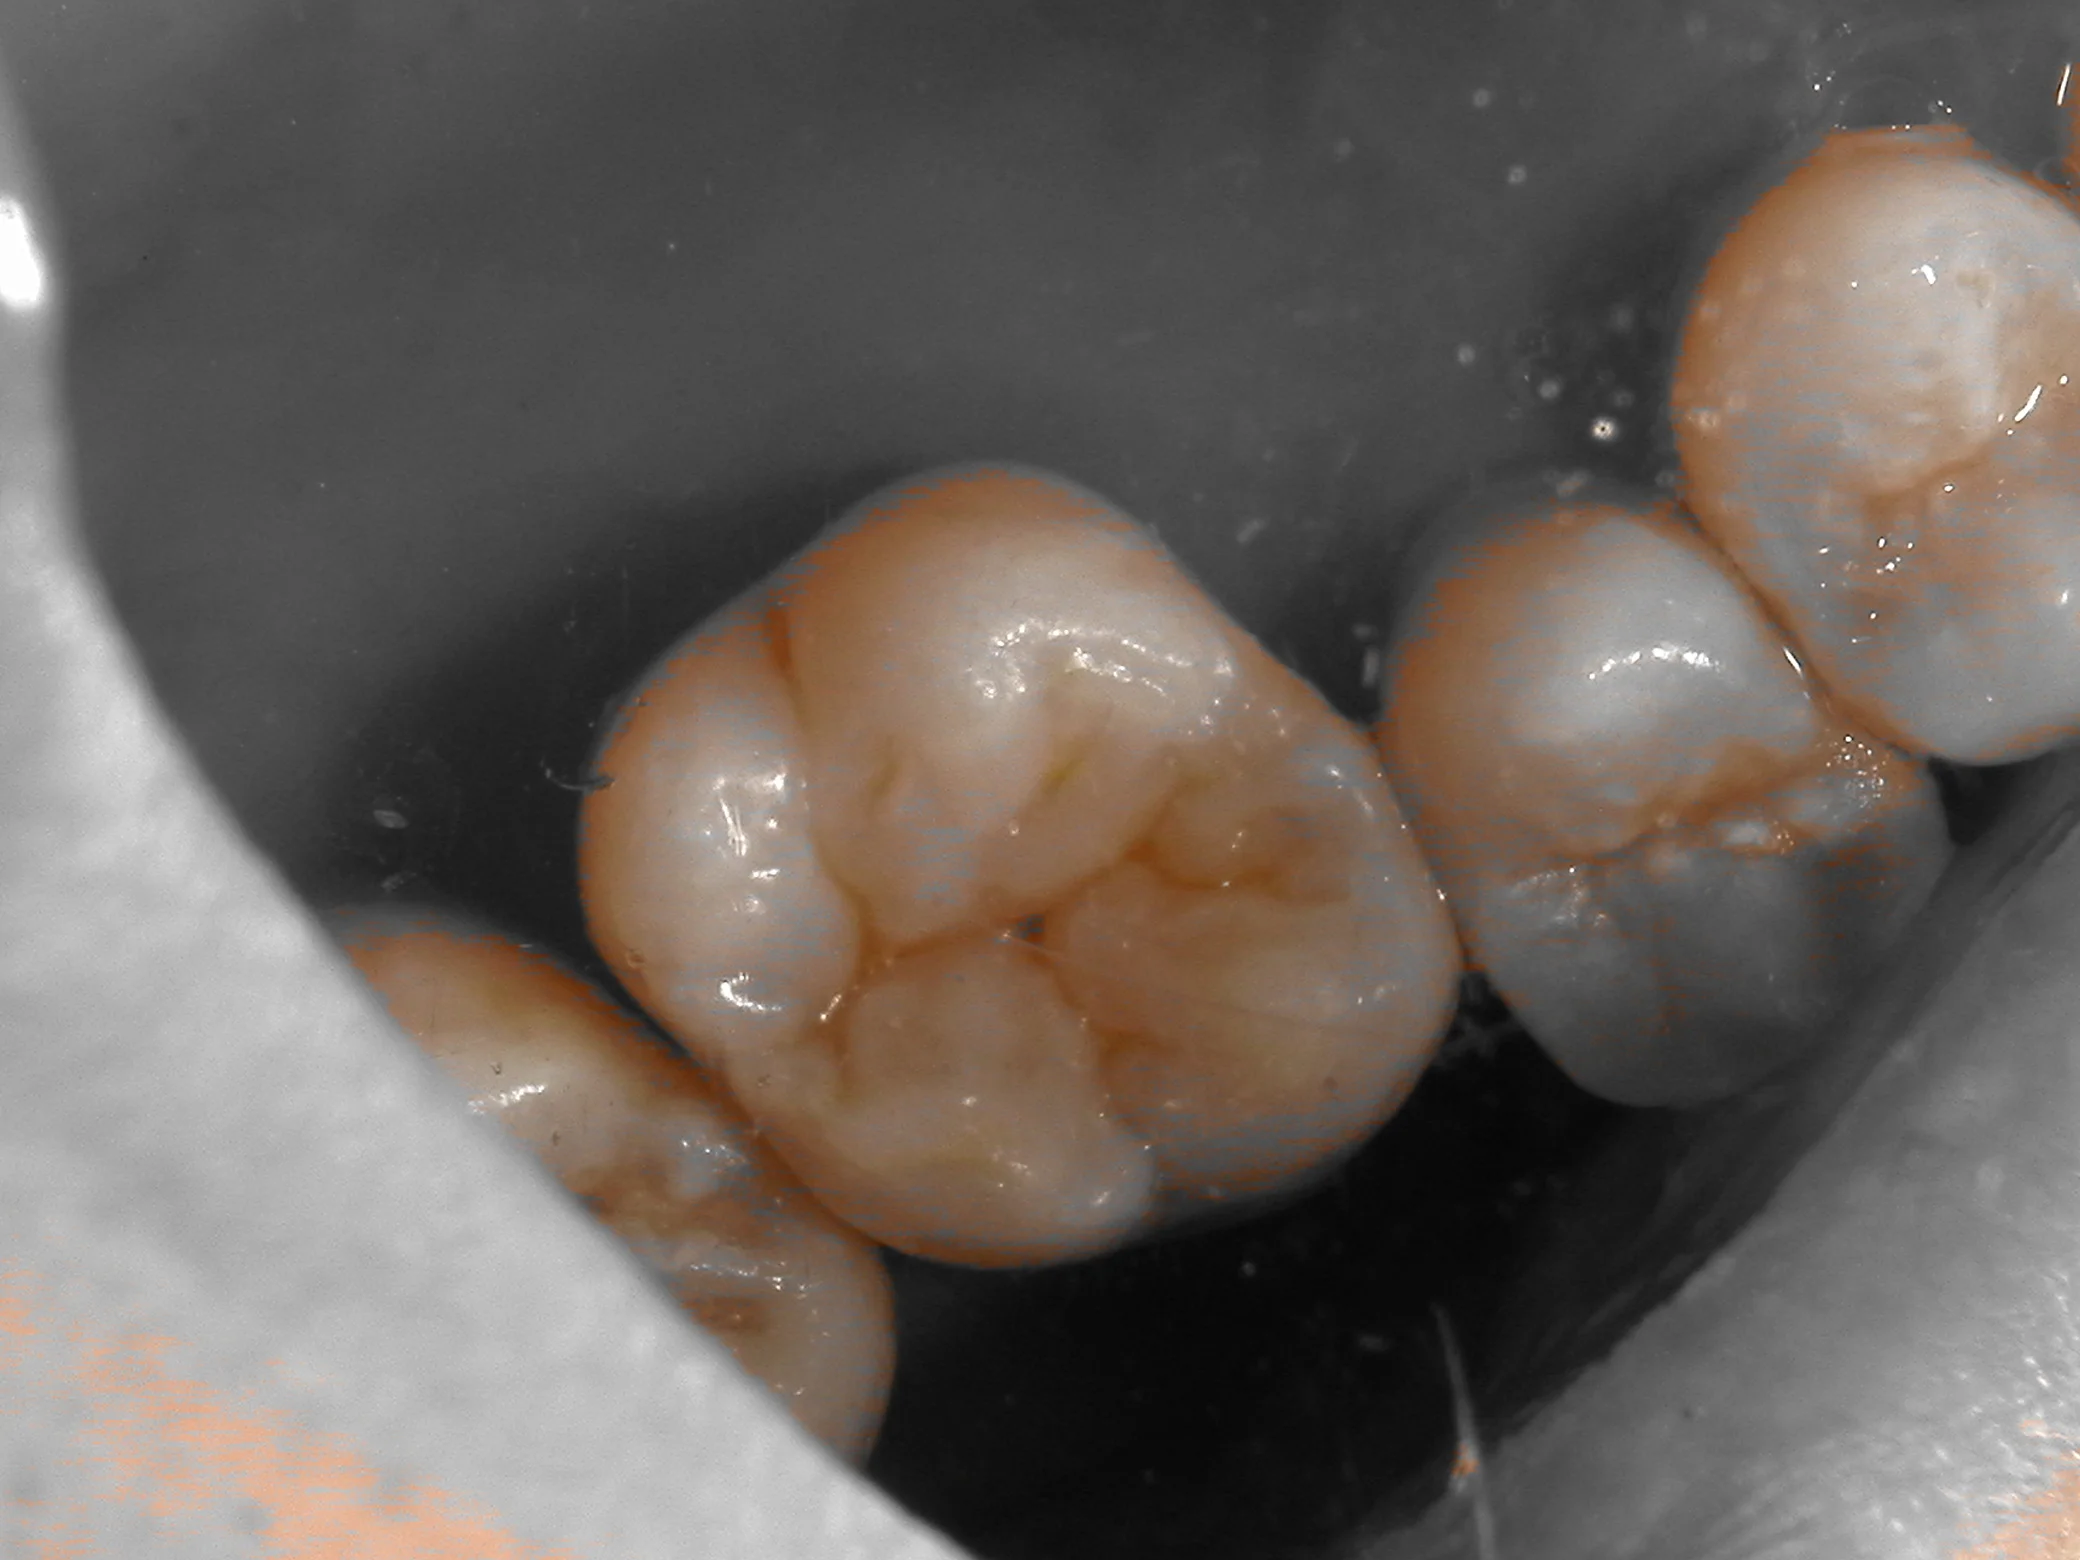

まず、普通の状態。

そして、色の違いを分かりやすくするためのシェード抽出画像。

どうでしょうか?

若干、中心裂溝(中央の黒い点)の深さを深くしすぎてしまった感じはありますが・・・

そこまで大きな色の違いは出ていないと思います。